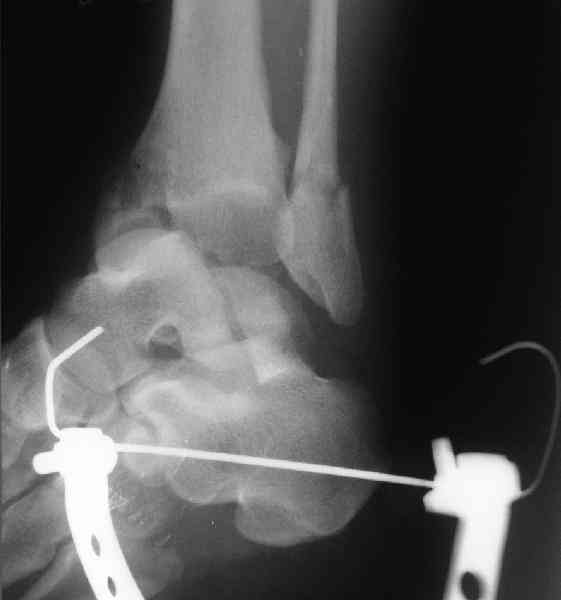

Решили не связываться с остеосинтезом, а сделать сразу берцово-пяточный блок. Снимки в приложении.

По завершении удлинения, наверно, заштифтуем.

Комментарии/критика приветствуются.